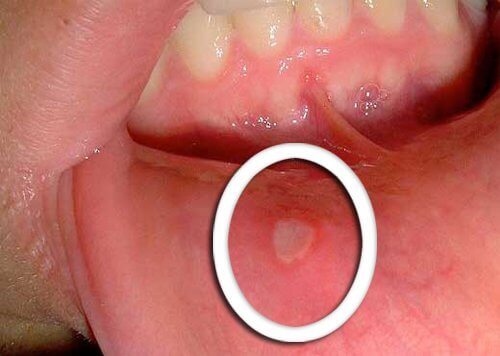

Fjerning av munnsår

Vask en del av avokadoskallet og tygg på det uten å svelge det. Spre spyttet som oppstår godt rundt i munnen. Gjenta dette flere ganger og spytt deretter ut avokadoskallet.